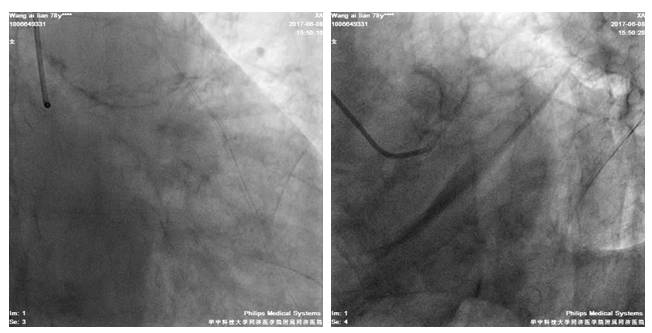

6F JR4.0/GC

BMW/GW

2.5*20mmTazuna扩RCA中段8-16atm

3.0*33mm DES置入RCA中段

3.5*36mmDES置入RCA近段10-14atm,与前支架串联

3.5*15mm Hiryu 扩RCA8-20atm

术后造影